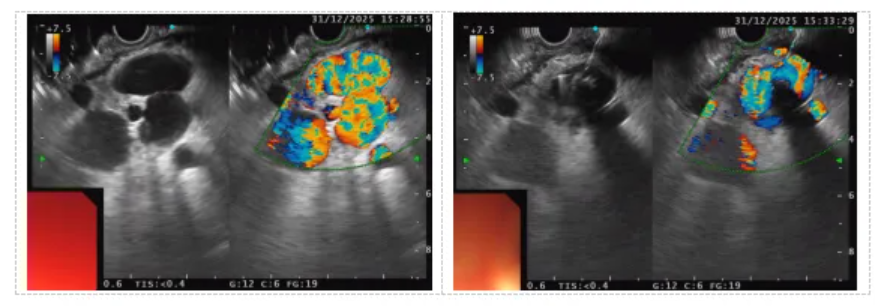

急诊内镜显示,患者食管静脉重度曲张,胃底情况更为复杂凶险:小弯侧可见粗大曲张静脉伴表面糜烂,疑为活动性出血点;大弯侧穹窿部则存在一直径约4厘米的巨大静脉瘤。进一步行超声内镜评估时,发现了一个致命隐患——“自发性胃肾分流道”(SGRS)。该异常血管通道在门静脉高压背景下形成,直接连接胃底曲张静脉与肾静脉,若按传统方法注射组织胶,极易导致胶体随血流异位栓塞至肺、脑等关键器官,引发致死性并发症。

在超声实时引导下,张宁主任经微细穿刺针将两枚微型弹簧圈准确送达目标血管,随后注入适量组织胶。弹簧圈迅速形成“钢筋骨架”,与凝固的组织胶(“混凝土”)紧密结合,在曲张静脉及异常分流道内构建起稳固的“钢筋混凝土”式栓子。超声屏幕上可见原活跃血流信号立即消失,表明出血源头被成功封堵。随后,团队对食管及其他胃底曲张静脉进行了套扎和加固治疗,一次性完成了多部位复杂静脉曲张的联合处理。